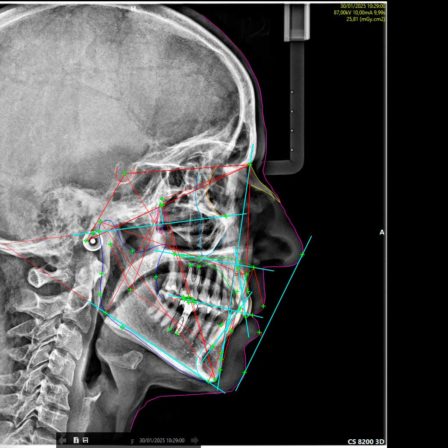

Servicio de Tomografía computarizada CBCT, ortopantomografía, telerradiografía y radiografías de ATM al momento

Mediante la radiología digital de baja radiación, podemos valorar estructuras de interés odontológico o craneal, con imágenes 2D o 3D, según sea el caso.